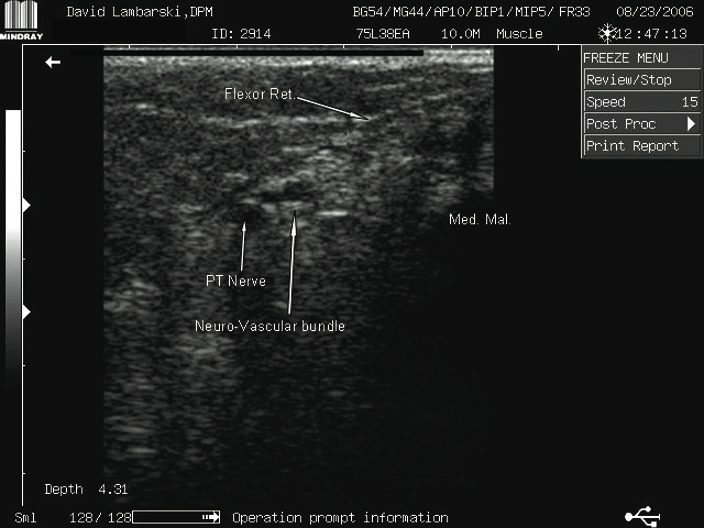

Combining Cryosurgery With Ultrasound: A Guide To Surgical Technique

The procedure involves palpating the posterior tibial artery just proximal to the level of the medial malleolus. We begin by providing anesthesia using a 1 cc syringe of 1% lidocaine with 100,000 dilution of epinephrine. One would inject this solution subcutaneously with a tuberculin syringe 2.5 cm superior to the medial malleolus directly over the posterior tibial artery. We proceed to prep the area in the usual sterile manner with Betadine® and protect the area with a Sound-Seal® thin film dressing (BioVisual Technologies), an FDA-approved protective film dressing for diagnostic ultrasound exams. Cover the area with the sterile dressing and mark the incision site using a sterile pen. A #11 sterile blade provides for a transverse 3 mm full-thickness skin incision. Take care not to violate any deeper structures. (In the aforementioned case study, we performed the procedure in the office under local anesthesia and without tourniquet assistance.) Using a blunt probe, gently penetrate the fascial tissue in the direction of the neurovascular bundle. Use the diagnostic ultrasound machine carefully to help create a tunnel for the cryosurgery probe. Insert the probe into the incision site while under the guidance of the diagnostic ultrasound scanner. We use the HydroStep® Standoff pad to help facilitate compliance over bony prominences such as the medial malleolus. The standoff pad also moves vital structures into specific ultrasound focus zones. The combination of compliance and the shifting of structures deeper into focus zones provides better image quality and resolution. Proceed to introduce the probe into the target area, namely the posterior tibial neurovascular bundle. Since the cryosurgery ice ball ranges in size of 3.5 to 10 mm, depending on environmental conditions, there is no need to dissect the nerve from its adjacent vein and artery. After inserting the probe with pressure directly on the neurovascular bundle, the freezing technique begins. This involves a three-minute freeze cycle, which causes an ice ball formation around the neurovascular bundle. One can directly visualize this process in real time using diagnostic ultrasound imaging. After the initial three-minute freeze, perform a 30-second thaw cycle followed by a second three-minute freeze cycle and 30-second thaw cycle. Generally, the ice ball will surround most of the neurovascular bundle as one can see on the diagnostic ultrasound screen. Once this cycle is completed, withdraw the probe. Dress the incision site with a sterile antibiotic ointment and a gauze compression dressing. No sutures are needed. Our general postoperative course involves no medications and no limitation of activity. The patient is able to shower the following day.